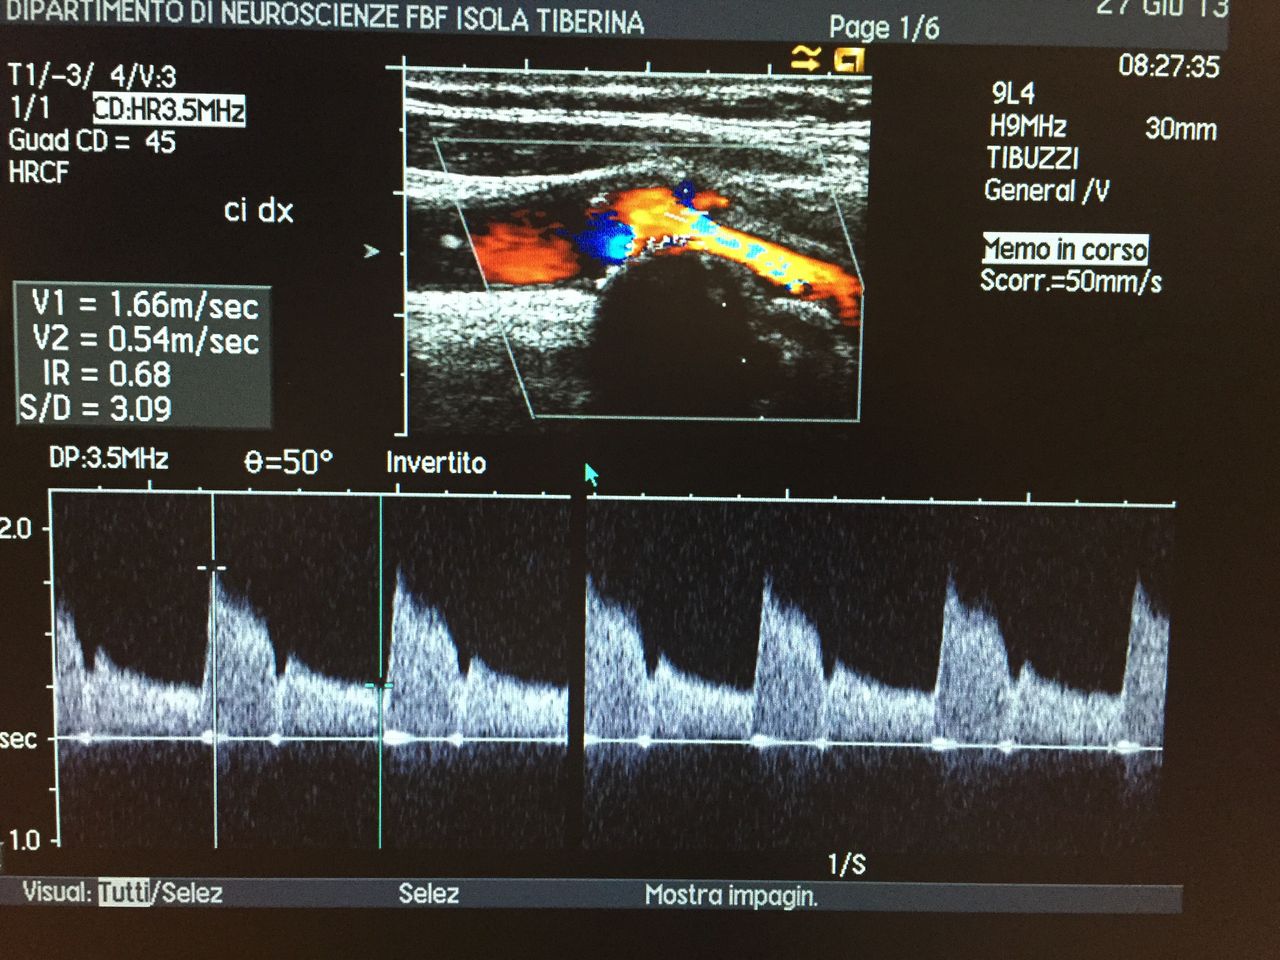

Specializzato in neurologia nel 2005 con il massimo dei voti, sin prima della laurea ho frequentato diversi ospedali romani dedicandomi alla clinica neurologica. Mi occupo delle patologie neurologiche in generale ed in particolare di cefalea e di malattie cerebrovascolari per le quali negli ultimi 15 anni ho maturato esperienza nella diagnosi e terapia in particolare nella diagnostica vascolare non invasiva in ambito clinico e di ricerca scientifica (ecodoppler vasi epiaortici e transcranico).

• Ecocolordoppler